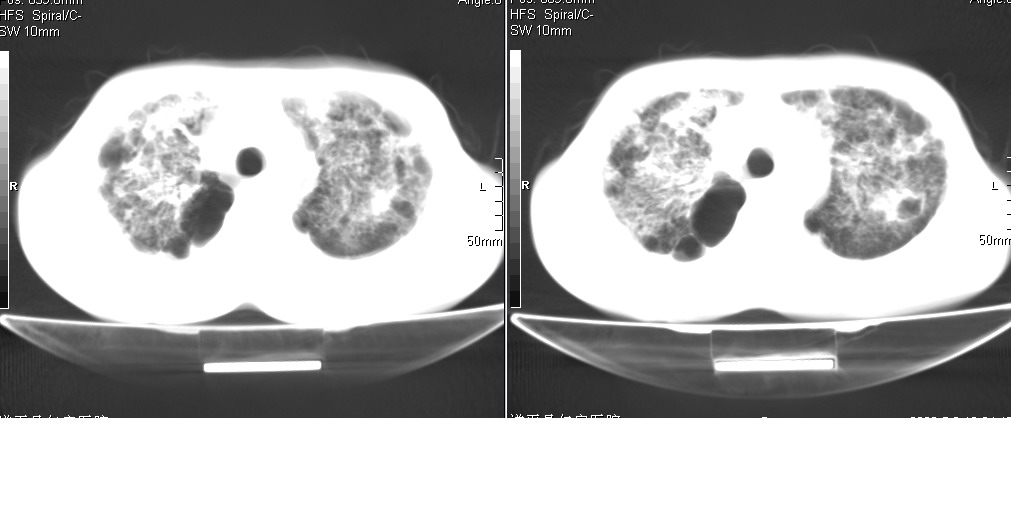

以下是引用光线在2008-5-6 18:36:00的发言:[br]双肺结核(左上肺空洞形成)、间质性改变合并感染,右肺大泡;右侧胸膜增厚。

以下是引用zsl6918在2008-5-7 1:54:00的发言:[br]首先肺泡蛋白质沉着症,其次考虑机遇性感染。